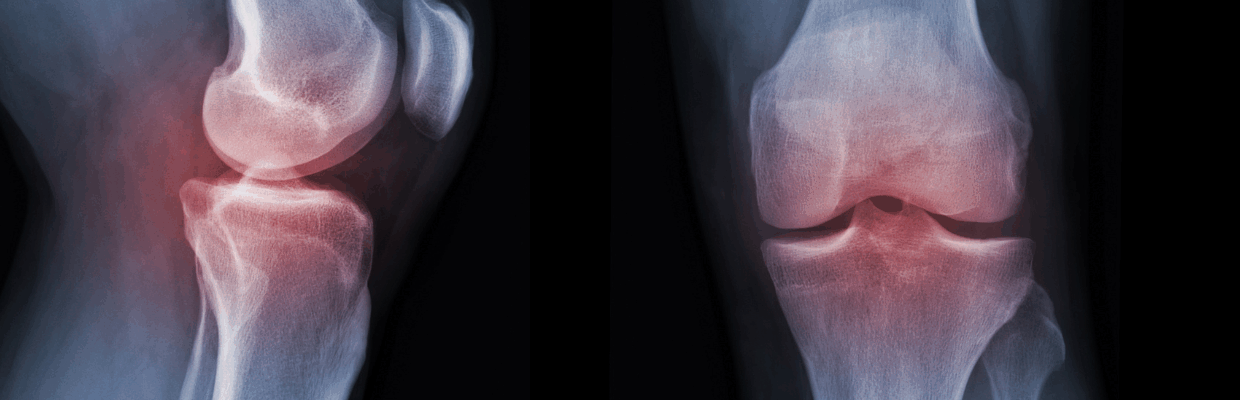

Sarcopenia is commonly seen in patients with rheumatoid arthritis where chronic inflammation contributes to the loss of muscle mass and strength. Currently, there are no approved medicines to reverse the effects of the condition.

As part of the RAMUS trial, 15 patients were given tofacitinib, a type of Janus kinase inhibitor (JAK). These medicines work by blocking immune system signals that lead to inflammation seen in conditions like rheumatoid arthritis.